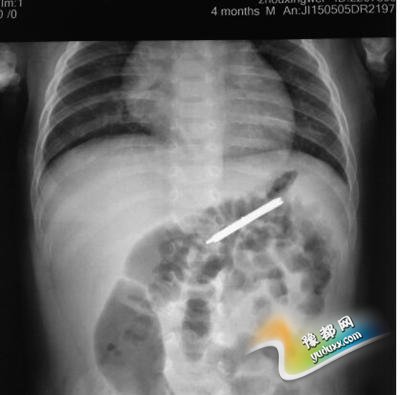

[摘要]从男婴胃里取出的折叠刀 X光片显示,折叠刀在男婴左上腹部 近日,澄迈县一4个月大的男婴意外吞下一把折叠刀,在胃里滞留5天后才在海南省农垦总医院成功取出。目前,男婴已顺利出院。医生提醒各位家长,要看护好自己的孩子,最好不要给小孩佩戴任何装饰物品,...

从男婴胃里取出的折叠刀从男婴胃里取出的折叠刀X光片显示,折叠刀在男婴左上腹部X光片显示,折叠刀在男婴左上腹部

5日下午,澄迈男子周先生带着4个月大的儿子焦急万分地来到海南省农垦总医院就诊。原来,4月30日,该男婴意外吞服一把折叠刀。事发后,家长辗转省内多家医院求诊,经腹部X光片显示,折叠刀滞留在左上腹部。其他医院的医生建议观察,看折叠刀能否随粪便排出。然而,5天了,折叠刀仍未排出,家长担心发生不测,便将孩子送到省农垦总医院,希望能将折叠刀取出。

接诊后,省农垦总医院非常重视,考虑到患儿年龄较小且异物较大,医院即刻联系麻醉科、儿科等相关医生紧急会诊。经讨论,决定对患儿进行内镜下消化道异物取出术。在麻醉科医生的协助下,患儿很快进入麻醉状态,考虑患儿消化道腔道细小、容易损伤等因素,医生选择了超细胃镜为患儿进行异物取出术。大约5分钟后,折叠刀顺利取出。据测量,折叠刀长约3.4 厘米,宽约1.0 厘米。